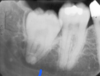

Name this type of radiograph

Periapical